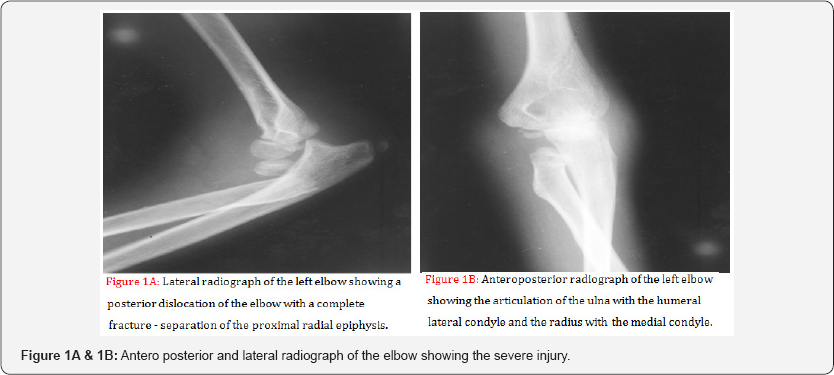

An eleven-year-old boy was admitted to hospital after a fall from a height, landing on his left arm. On examination the elbow was deformed and held in flexion of about 80°. There were no neurovascular deficits. The radiological examination showed a posterior dislocation of the elbow and a displaced Salter - Harris type II epiphyseal injury of the proximal radial epiphysis. The antero posterior radiograph was the cause of a more careful observation of it, where it was found, that the radius and ulna were reversely articulated with the distal humerus (Figures 1 A & 1B).